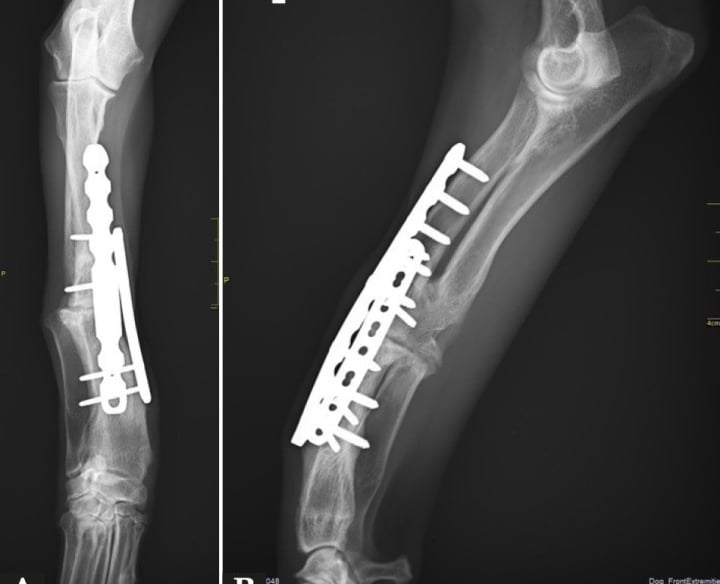

La placa se posiciona sobre el hueso afectado, adaptándose a su anatomía sin necesidad de comprimirlo directamente.

Los tornillos se introducen atravesando la placa y se enroscan en ella, quedando firmemente anclados tanto al hueso como a la placa.

Al bloquearse los tornillos con la placa, se crea una estructura estable tipo “armazón” que no depende de la presión sobre el hueso.

El sistema mantiene los fragmentos óseos alineados, permitiendo una adecuada recuperación y favoreciendo la cicatrización.

Los sistemas de placa bloqueada ofrecen ventajas significativas frente a métodos tradicionales, ya que combinan estabilidad mecánica con un enfoque más biológico de la reparación ósea.

Mayor estabilidad

La fijación entre tornillo y placa crea una estructura rígida que mantiene los fragmentos óseos alineados incluso en fracturas complejas.

Al no requerir compresión directa contra el hueso, se reduce el daño a los tejidos blandos y se conserva mejor el riego sanguíneo, clave para la cicatrización.